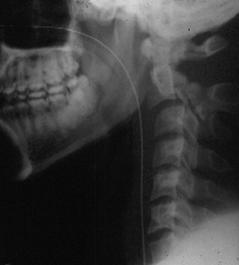

TRAUMA CERVICALA

Incidenta laterala Incidenta

Aspect normal Imagine

normal